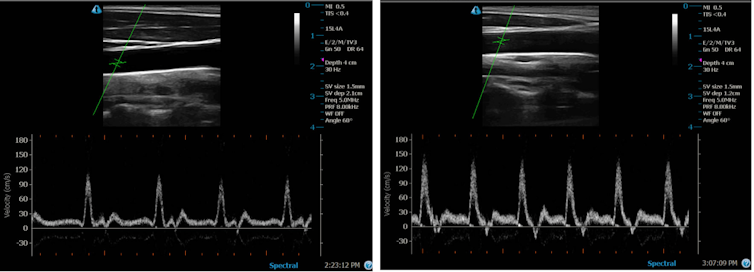

The similarities also go beyond what you can physically feel. By doing ultrasound scans of the arteries, I also observe similar increases in blood flow.

When your temperature begins to rise, you must find a way to lose excess heat in order to regulate body temperature. One of the principal mechanisms that facilitates heat dissipation from the body is an increase in blood flow to your skin, which is in part supported by the vasodilation (widening) of your arteries and capillaries. This elevation in blood flow, which I measure through ultrasound scans, also promotes the production of various molecules in the blood that help cell growth, repair and protection of your blood vessels.